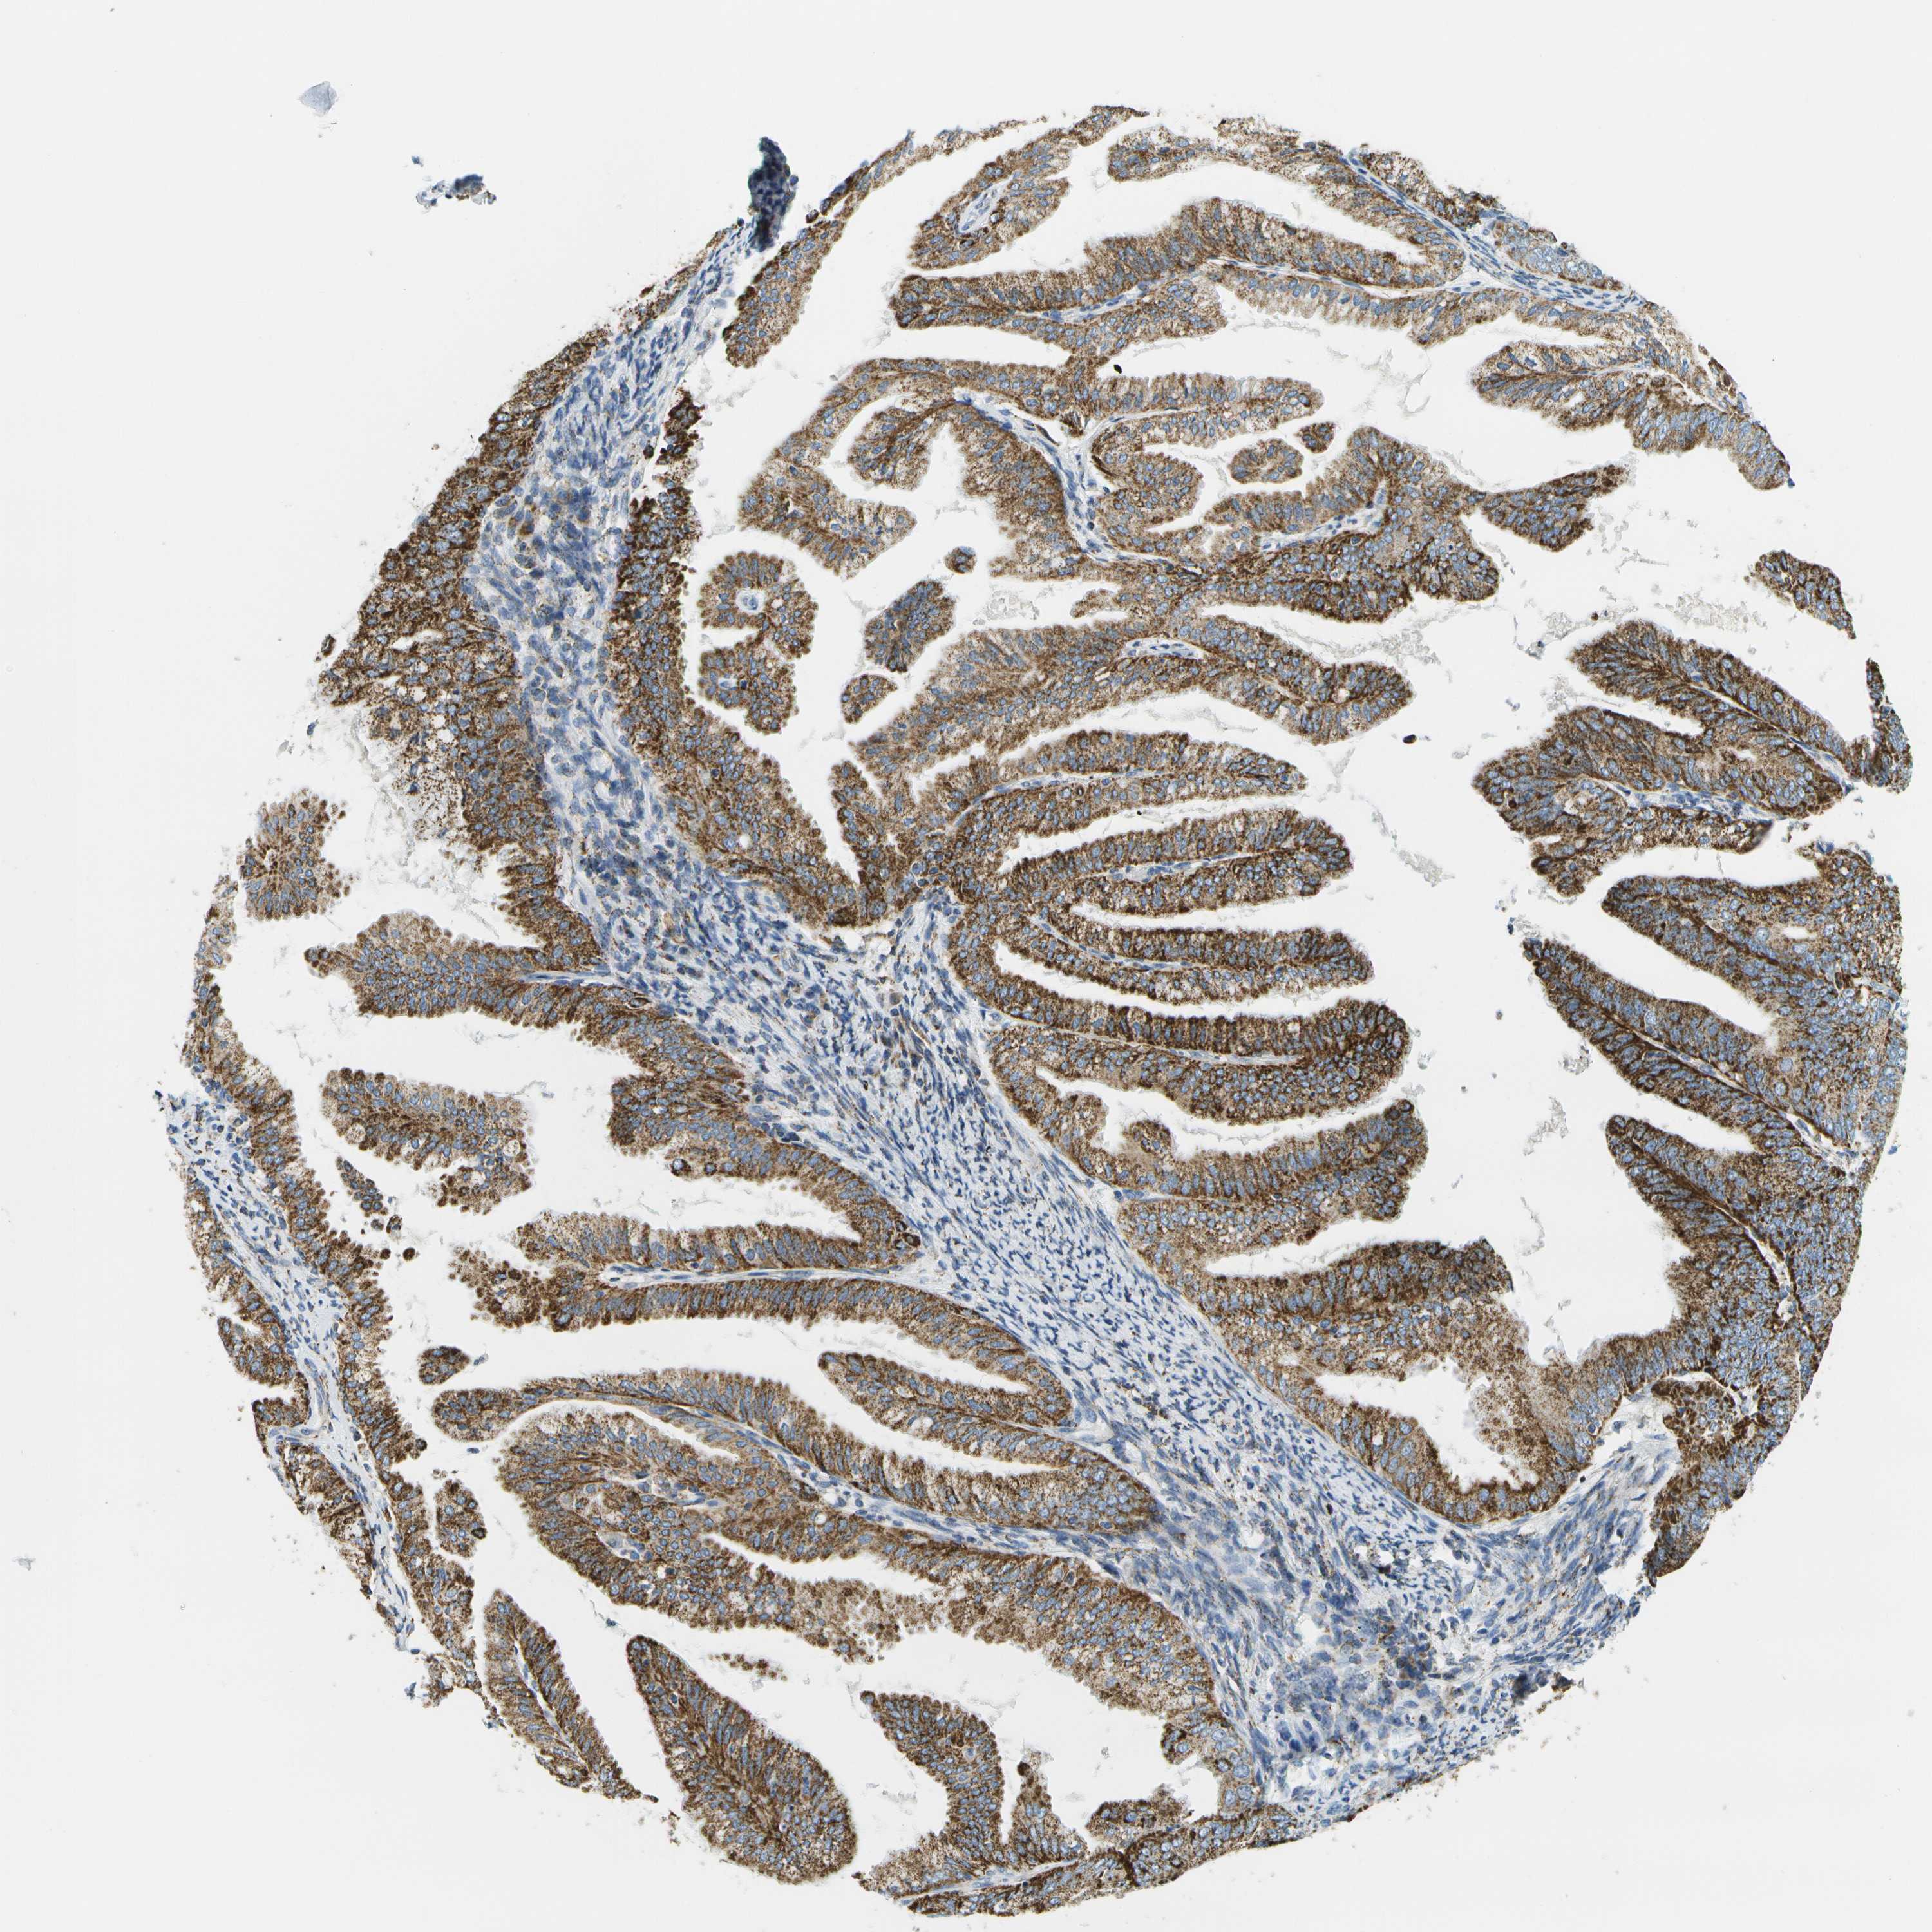

ENDOMETRIAL CANCER - Protein expressioni

A mouse-over function shows sample information and annotation data. Click on an image to view it in a full screen mode. Samples can be filtered based on level of antibody staining by selecting one or several of the following categories: high, medium, low and not detected. The assay and annotation is described here.

Note that samples used for immunohistochemistry by the Human Protein Atlas do not correspond to samples in the TCGA dataset.

Antibody stainingi

Antibody staining in the annotated cell types in the current human tissue is reported as not detected, low, medium, or high, based on conventional immunohistochemistry profiling in selected tissues. This score is based on the combination of the staining intensity and fraction of stained cells.

Each image is clickable and will lead to virtual microscopy that enables deeper exploration of all samples and also displays staining intensity scores, fraction scores and subcellular localization as well as patient and tissue information for each sample.

Antibody HPA017379

Staining

High

Medium

Low

Not detected

Intensity

Strong

Moderate

Weak

Negative

Quantity

>75%

75%-25%

<25%

None

Location

Nuclear

Cytoplasmic/membranous

Cytoplasmic/membranous,nuclear

Adenocarcinoma, NOS